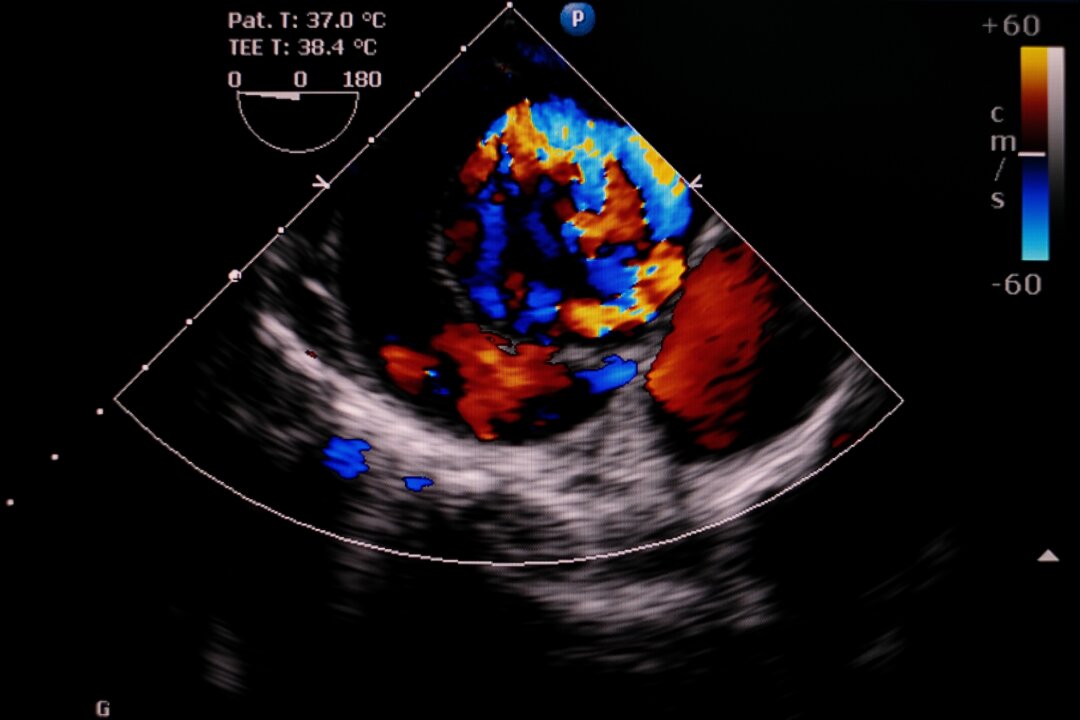

Aortic dissection after COVID-19